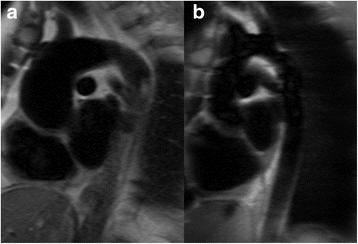

The distribution of flow patterns is shown in Fig. 2. The majority of BAV patients with a mechanical AVR (73%) and those who had a previous Ross procedure (67%) showed normal aortic flow patterns compared to benchmark patients with a native BAV, in whom only a minority had normal flow patterns (17%). In contrast, the AVR-tissue group demonstrated abnormal helical flow patterns in all patients (Fig. 3).

Typical ascending aortic flow patterns after aortic valve replacement (AVR); a – healthy subject with a laminar flow pattern; b – native bicuspid aortic valve disease with a right-handed helical flow pattern; c – AVR-mechanical with 2 laminar jets; d – AVR-tissue with a right-handed helical flow pattern; e – AVR-Ross with a laminar flow pattern

Recent advances in CMR imaging have suggested that the flow pattern in the ascending aorta is a major contributor to the aortopathy in BAV [2,3,4,5]. The marked helical flow pattern with an increased wall shear stress is thought to play an important role in the pathophysiology. However, very little is known about how flow patterns and wall shear stress are influenced by AVR. Our small study suggests that both the AVR-mechanical and Ross group appeared to have near normalization of flow haemodynamics following AVR, while abnormal helical flows appeared higher in the AVR-tissue group. The findings were similar in the cross-sectional assessments and in those imaged before and after AVR. The numbers in some groups (particularly the AVR-tissue group) were small however and this limits the strength of conclusion. If true, one explanation for this phenomenon may be that a bioprosthetic AVR is inherently associated with increased rotational flow. Abnormal helical flows post-AVR have also been shown in other studies following bioprosthetic AVR for trileaflet aortic valve disease [8, 15,16,17], supporting the limited data in our study. The pathophysiology for this would be unknown however. We note that all patients with a bioprosthetic AVR imaged pre- and post-surgery had a right-handed helical flow pattern after AVR, even though 2/6 of these patients had had a complex flow pattern pre-operatively, which may suggest that the bioprosthetic valve introduced a right-handed helical flow pattern in those with complex flow preoperatively. An alternative explanation may lie with the age at which the operation occurs. Bioprosthetic AVR is more prevalent in older patients, as was the case in our AVR-tissue group, and bicuspid aortopathy increases with age. At the later age of the bioprosthetic AVR, patients may already exhibit larger aortas with the ‘typical’ anteriorly bulging shape (Fig. 7) [18], and a trileaflet bioprosthetic AVR may not be enough to normalize the flow pattern in this setting. In contrast, the Ross procedure is normally undertaken in childhood before much of the aortopathy has developed, and it is conceivable that replacing the diseased bicuspid aortic valve with a (trileaflet) homograft may normalize the flow at this earlier stage, as observed in our study. A mechanical AVR, on the other hand, introduces a non- physiological flow pattern consisting of two parallel flow jets arising off-center, which our data suggests may reduce the overall rotational flow, even in the presence of a dilated aorta. Confirmation of this would however be required in larger studies.